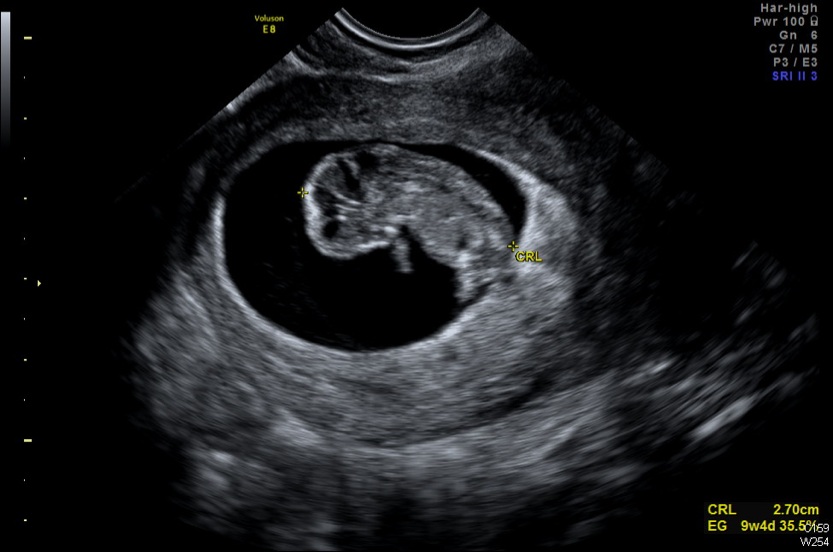

El nuevo sistema de IA fue entrenado para identificar con precisión los escasos espermatozoides presentes entre el material celular. Gracias a esta herramienta, fue posible encontrar uno viable y utilizarlo para fecundar un óvulo, lo que finalmente resultó en un embarazo exitoso.

Este avance abre nuevas posibilidades para miles de parejas que enfrentan desafíos similares, ofreciendo esperanza en situaciones que antes se consideraban sin solución.